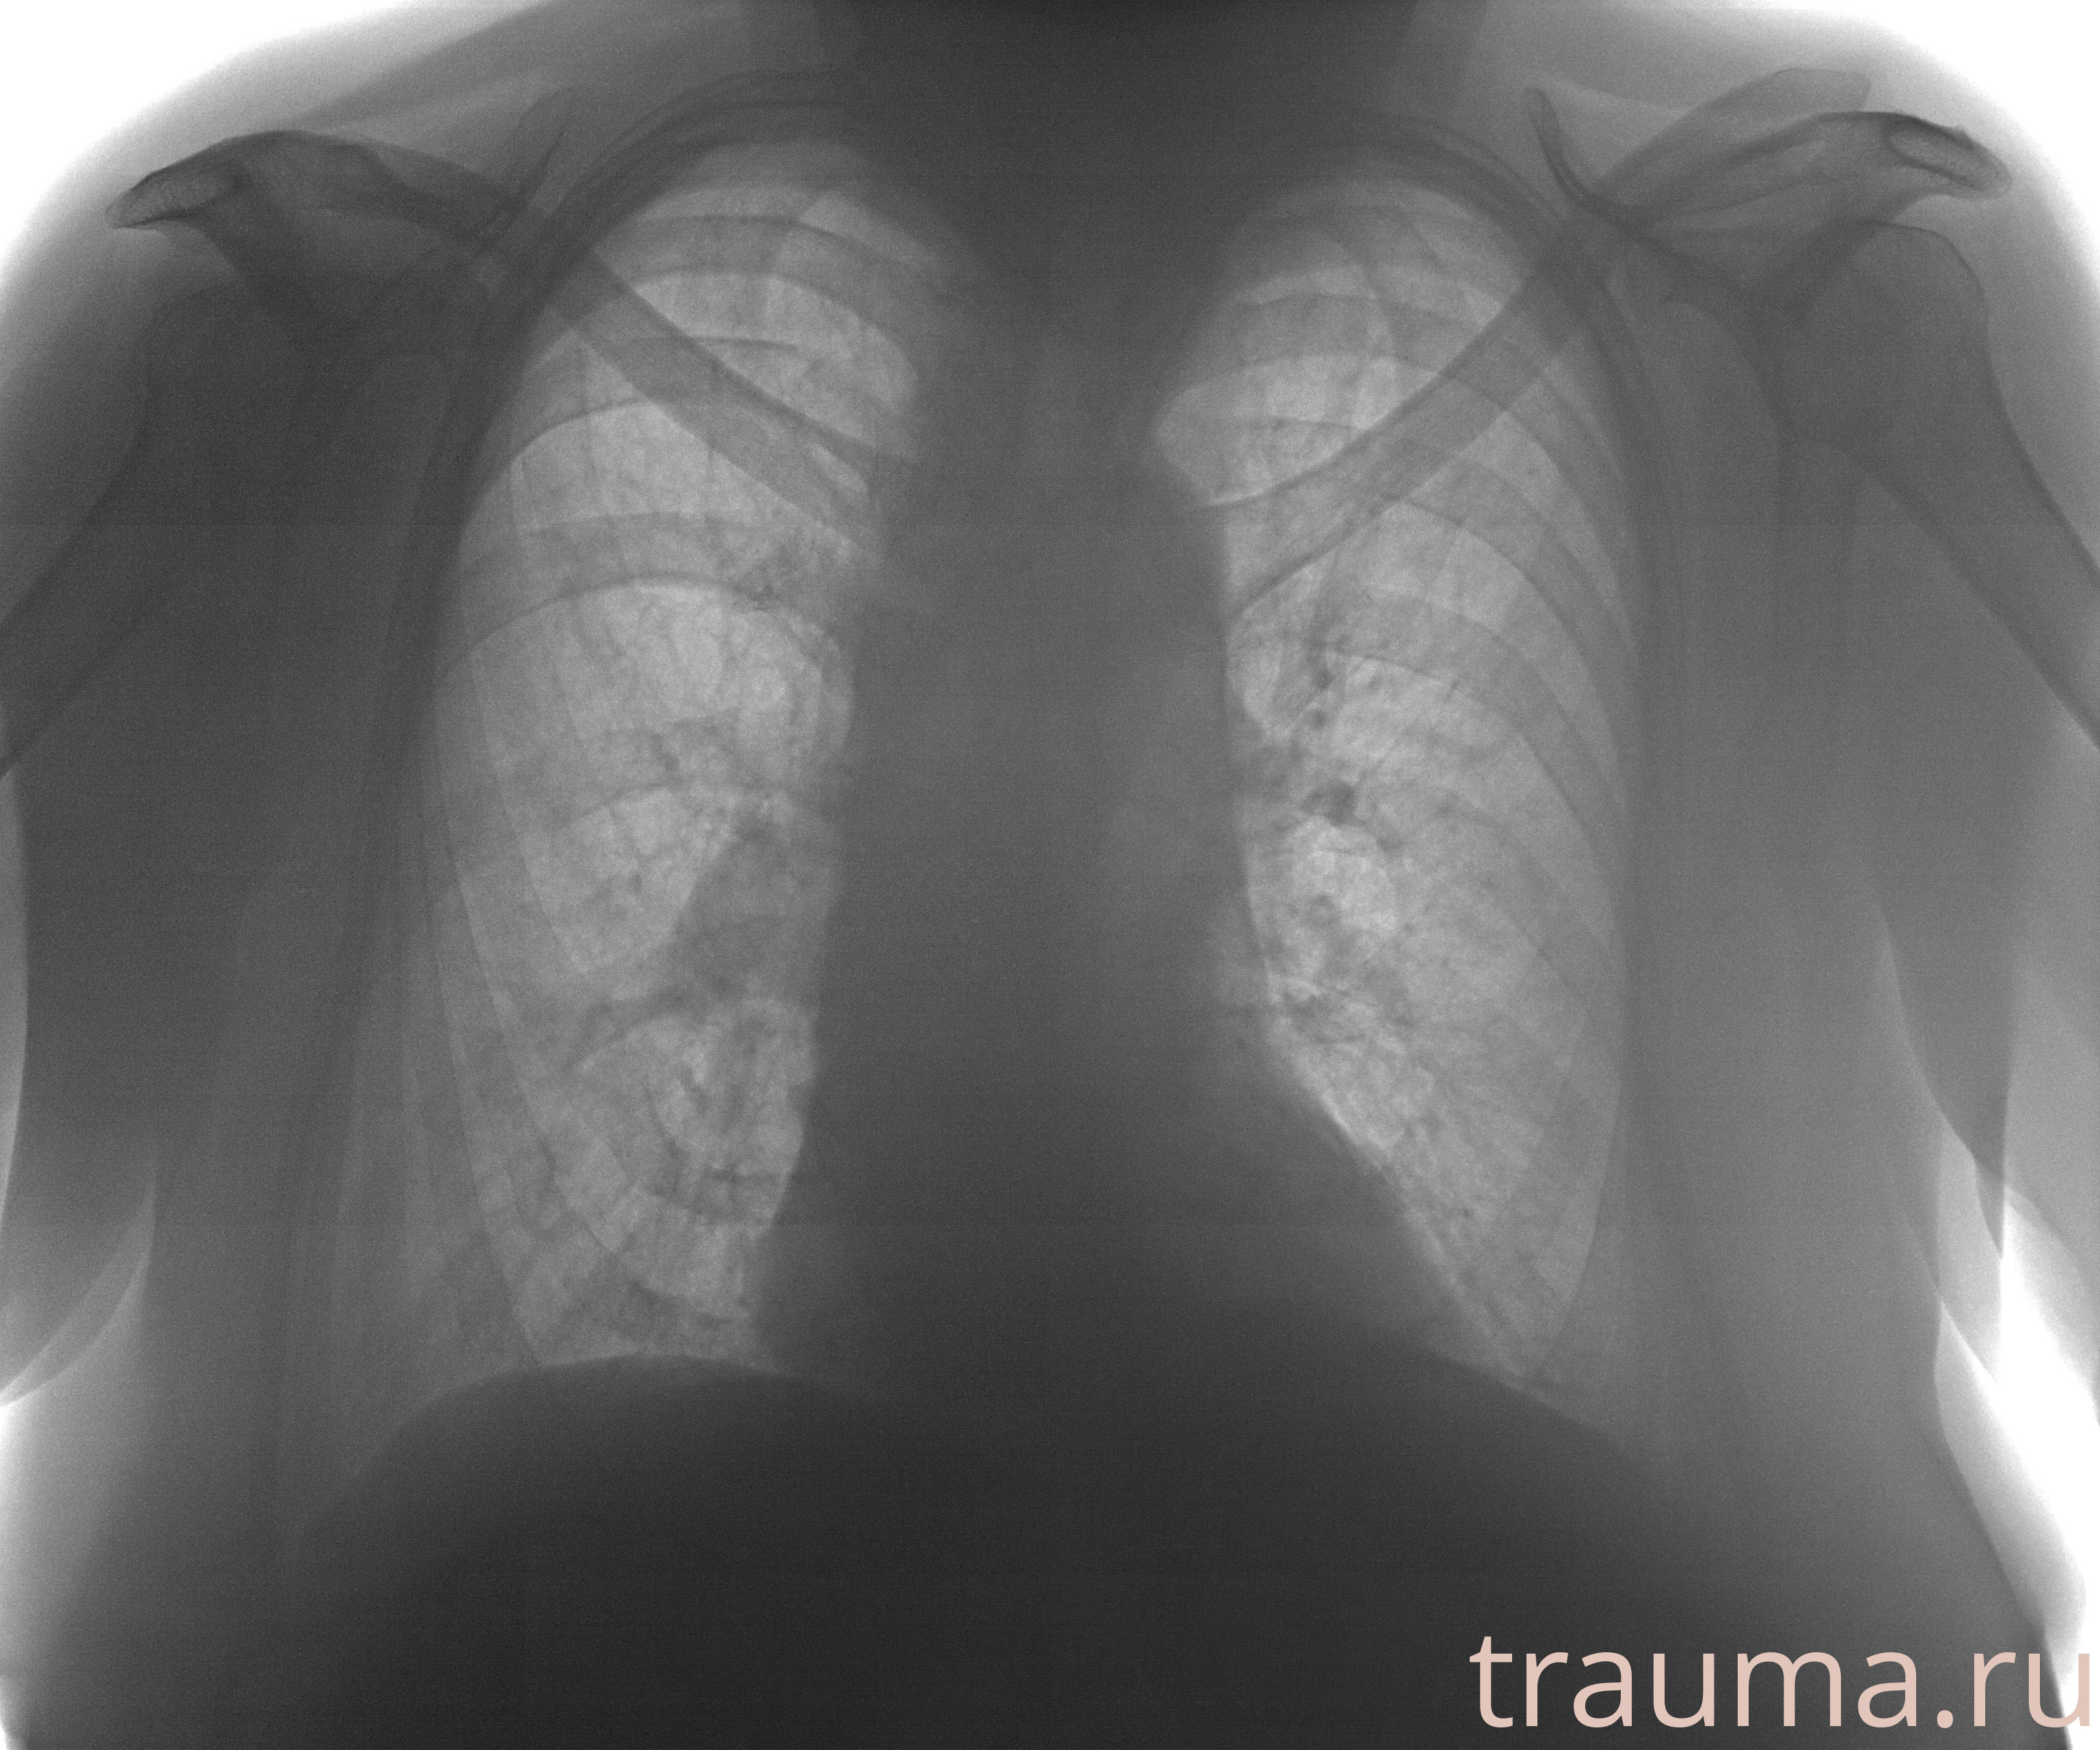

Рентген на дому: по вашему адресу приезжает врач-рентгенолог, травматолог-ортопед с мобильным рентгеновским аппаратом, проводит диагностику травмы или заболевания, делает необходимые рентгенограммы, дает рекомендации по дальнейшему лечению. Получить качественные снимки в домашних условиях возможно благодаря уникальной методике, разработанной МосРентген Центром для института  Склифосовского